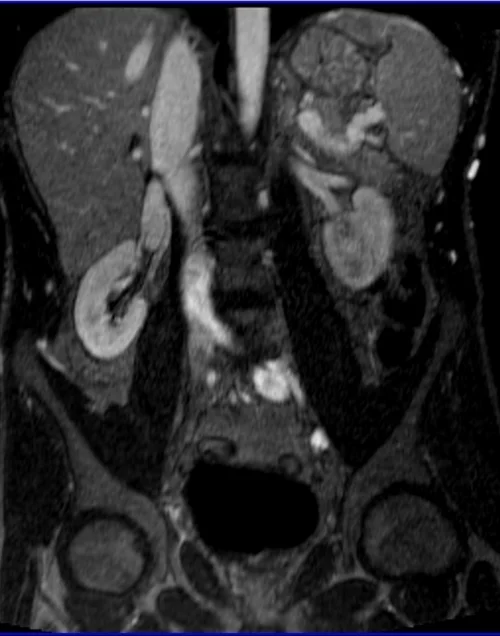

MRA Renal Arteries